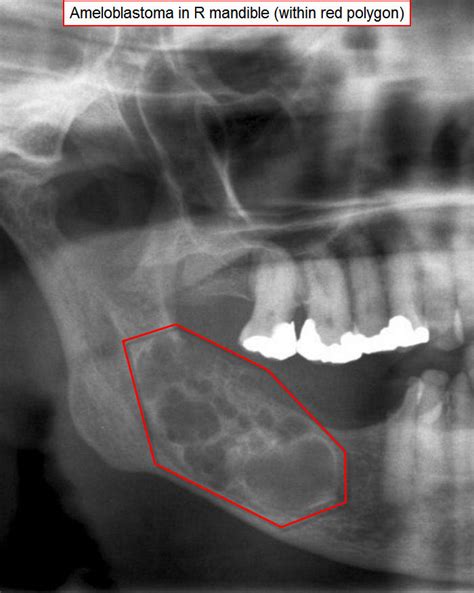

Radiografía que muestra un ameloblastoma multilocular en la mandíbula.

Radiológicamente suele describirse como una lesión quística expansiva que adelgaza o erosiona la cortical ósea.

Se han descrito 3 patrones radiológicos de esta lesión: unilocular, multilocular y en panal de abejas.

Con las pruebas de imagen obtenemos el patrón de presentación radiológica: unilocular (25%), multilocular (56,25%) o en panal de abejas (18,75%).